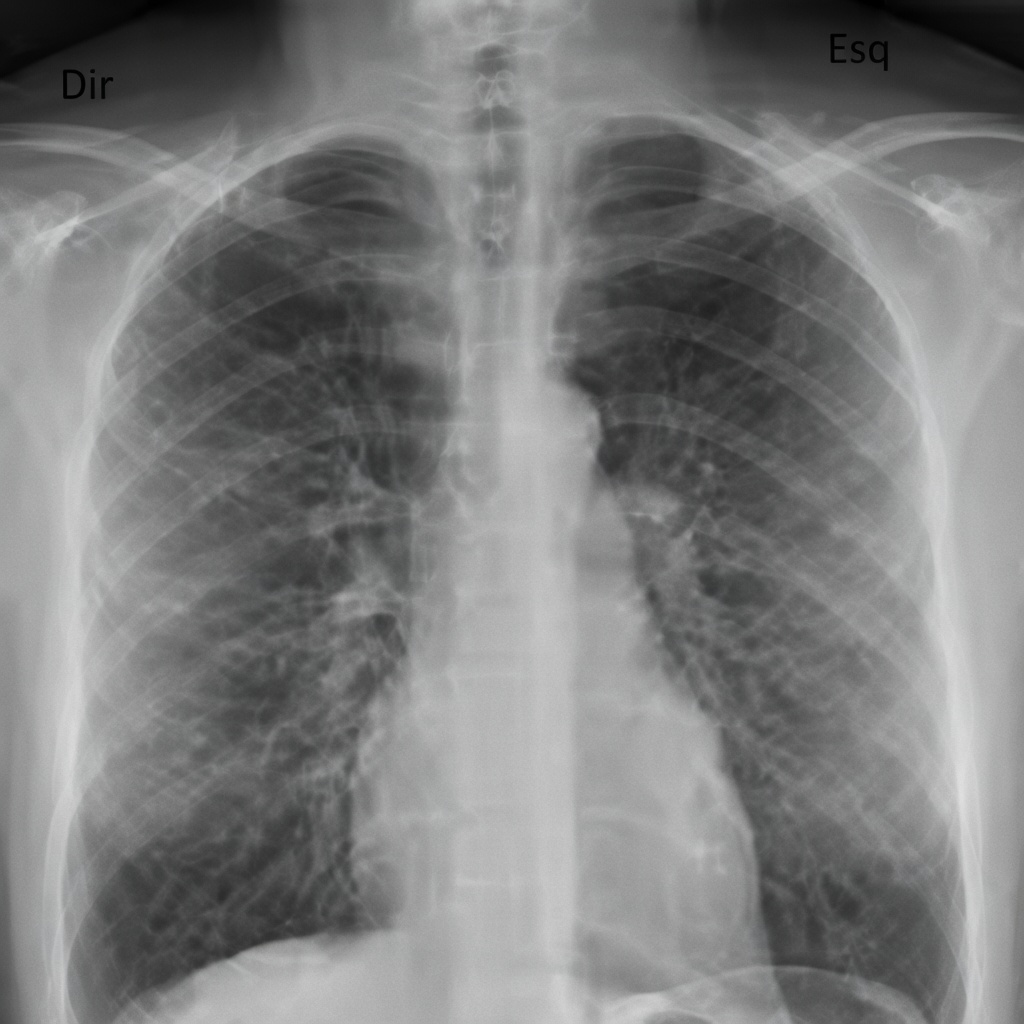

4. Raio-X de tórax de rotina — pouco útil em não fumantes sem sintomas respiratórios

O raio-X de tórax anual é um exemplo clássico de exame de saúde a evitar em pessoas que não fumam e não têm sintomas respiratórios (tosse persistente, falta de ar, dor torácica, febre prolongada). Ainda que a radiação seja menor do que a de uma tomografia, há dois pontos importantes:

- exposição desnecessária, mesmo que pequena

- risco de achados incidentais que não são perigosos, mas geram investigação

Diretrizes atuais de organizações médicas recomendam que o raio-X seja feito de forma direcionada (quando há indicação), e não como “check-up padrão”.